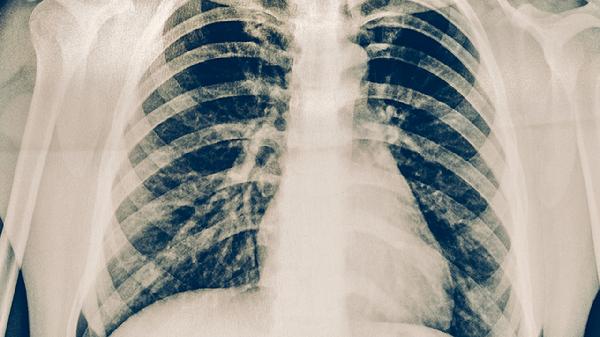

肺心病患者的護(hù)理

肺心病患者可通過(guò)氧療護(hù)理、飲食護(hù)理、運(yùn)動(dòng)護(hù)理、藥物護(hù)理、心理護(hù)理等方式改善病情。肺心病通常由慢性阻塞性肺疾病、肺動(dòng)脈高壓、心肌缺氧等因素引起,可能伴隨呼吸困難、下肢水腫等癥狀。